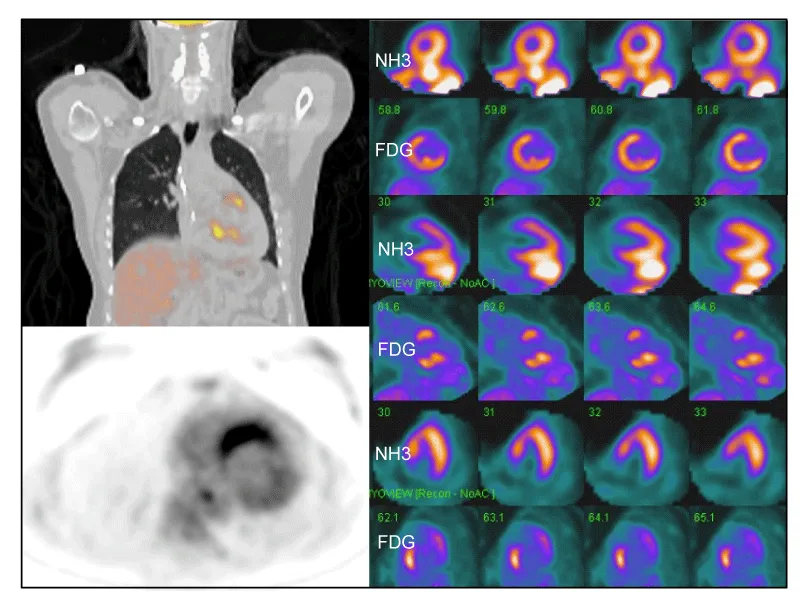

18FDG-PET has been used to diagnose and “stage” sarcoidosis in thoracic and extra-thoracic sites [126-128], including CS [94,124,127,129,130] (Figures 2-6). Increased update of 18FDG occurs within activated leukocytes, macrophages, and CD4+ T lymphocytes, major components of granulomas [128], and correlates with inflammation in the lung or extra-pulmonary sites [126,127]. 18FDG-PET is a sensitive marker of disease activity in sarcoidosis [129,131] and is superior to Ga67-citrate [132] and Tl 201-scans [133] to diagnose CS. The specificity of PET as a diagnostic tool in CS relies on the suppression of normal myocyte uptake of glucose. For this reason, prolonged fasting ( > 12 hours) and fatty acid loading [134,135] are required before imaging to suppress myocardial glucose metabolism in favor of oxidation of free fatty acids [136]. PET scans in CS may show different patterns of diffuse and focal uptake (Figure 2) [137]. Three basic patterns in CS have been observed: diffuse, focal, and focal on diffuse; perfusion abnormalities may also be present [102] (Figures 4-6). In an early study in Japan, 17 cases of CS had 18FDG-PET, Tl201, and Ga67 scans [133]. 18FDG-uptake in the heart was increased in 14/17 (82%) whereas abnormal myocardial uptake was noted in only six (35%) and three (18%) cases on Tl201 or Ga67 scans, respectively. 18FDG-PET scans were repeated in seven patients after one month of steroid therapy; 18FDG defects disappeared entirely in five and improved in two [133]. In 2012, a meta-analysis of all studies relevant to 18FDG-PET to diagnose CS reported pooled sensitivities and specificities of 89% and 78%, respectively [105].

Focal perfusion defects and 18FDG uptake on PET in patients with suspected CS assess the presence or absence of inflammation [35,36,134]. Early in the course of CS, PET may show focal 18FDG uptake at sites of granulomatous inflammation without associated perfusion defects [35]. In later stages, after the inflammation has “burned out”, perfusion defects may persist whereas 18FDG uptake resolves [35]. Serial PET scans have been used to evaluate response to therapy in CS and prognosis [36-38,133,138] but randomized trials are lacking. Reduction in 18FDG uptake has been noted following therapy with steroids and has been associated with improved prognosis [37,133,139]. Serial PET scans were performed in 16 patients with CS before and during treatment [36]. Quantitative assessment of 18FDG-avid cardiac lesions was interpreted via four PET parameters; the clinical response was evaluated by symptoms and clinical criteria. Quantitative PET parameters significantly declined (inflammation improved) on repeat PET in patients who clinically were stable or improved whereas those whose PET had not improved were clinically worse [36]. Shelke, et al. evaluated 15 patients with CS who had PET scans before and after initiation of steroid therapy (126 +/- 54 days post) [37]. Four cases were considered non-responders [defined as lack of improvement or worsening in clinical outcomes (i.e., VA, HF, LV systolic function) despite steroid therapy]. Myocardial maximum standardized uptake of 18FDG (SUV max) declined (improved) significantly in 11 patients responding to steroids (p = 0.004) but increased in non-responders (p < 0.05) on follow-up. Further, the number of LV segments with 18FDG uptake declined significantly in responders (p = 0.007) but trended towards increase in non-responders (p = 0.465). Importantly, heterogeneous uptake on baseline PET and increase in intensity and area of myocardial involvement on follow-up were associated with poor clinical outcomes despite steroid therapy [37]. In another study of 118 cases with known or suspected CS, 18FDG-PET scans were abnormal in 71 (60%) [134]. Over a median follow-up of 1.5 years, Adverse Cardiac Events (ACE) occurred in 31 (26%) and included 27 episodes of VT and 8 deaths. Cardiac PET findings were predictive of ACE; the presence of both a perfusion defect and abnormal 18FDG update (29% of patients) was associated with an HR of 3.9 (p < 0.01) for ACE and remained significant after adjusting for LVEF and clinical criteria [134]. Serial 18FDG-PET scans were done in 34 pts with CS (mean of 4 per patient during 2.3 years of follow-up) at Stanford (USA) from 2010-2017 [38]. Presenting symptoms included advanced HB [n = 12 (35%], HF [n =12 (35%)], and VA [n = 14 (41%)]. At baseline, PET showed increased cardiac 18FDG uptake in 27/34 (79%), consistent with active CS; seven (21%) showed no active CS. The most common pattern was patchy uptake (n=21); four showed patchy on diffuse 18FDG uptake. At a median follow-up of 2.3 years, 25 patients (74%) had received prednisone (pred) and 26 (76%) had been treated with pred + methotrexate (MTX). Nine (26%) received tumor necrosis factor-a (TNF-α)-antagonists after failing pred + MTX. At follow-up, 48% of patients had been weaned from pred completely and 20% were on a low maintenance dose (5 to 10 mg). Overall, two patients (6%) had died (one due to infection) [38].

While 18FDG-PET is a pivotal test in patients with CS for initial diagnosis and follow-up, pitfalls have been noted including 1) physiological uptake of 18FDG in myocardium may be found in healthy subjects; 2) normal myocardium may exhibit increased physiologic uptake on the basal and lateral LV walls; 3) apparent increased uptake of 18FDG in myocardium may reflect diet (i.e. not adhering to a low carbohydrate/high-fat diet for at least 12 hours prior to the test); 4) pulmonary hypertension increases RV and IVS 18FDG update because of the mechanical overload; 5) nonspecific 18FDG uptake may be observed in patients with non-sarcoid dilated cardiomyopathies; 6) interpretation may not be straightforward [3]. Artifactual inhomogeneities in PET may be seen in normal myocardium due to the influence of in-plane resolution and wall thickness [140]. Although 18FDG-PET has assumed an important role to diagnose and follow CA sarcoidosis, many centers combine 18FDG-PET with Gd-CMR to diagnose and follow CS [38,40,42,104,125,141,142], as these dual procedures may provide complementary information. 18FDG is more sensitive for early phases of inflammation, but Gd-CMR is more specific for later phases of scar formation [143,144]. Unfortunately, PET-CT and CMR are incredibly expensive (often > $10,000 per study in the USA) and may not be covered by insurance.